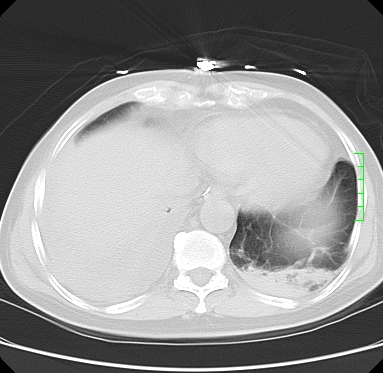

icu病人,几天都没明确诊断。m,76y,咳嗽、咳痰1周,伴气促,右胸痛入院,pe:t38.3c p135 r25 bp135/85。双肺可闻及大量湿罗音,心、腹未见明显异常。诊断:1心衰?2肺部感染?3冠心病?

11号ct

双肺感染性病变,下叶膨胀不全,胸水,左室大。

1)两肺感染性病变(右肺下叶肺脓肿可能)。2)双侧胸腔积液,以右侧为甚。

ards,肺感染性病变,右下叶实变,双侧胸腔积液,右侧为著,叶间胸膜积液,右上肺陈旧性tb纤维灶,左室大。